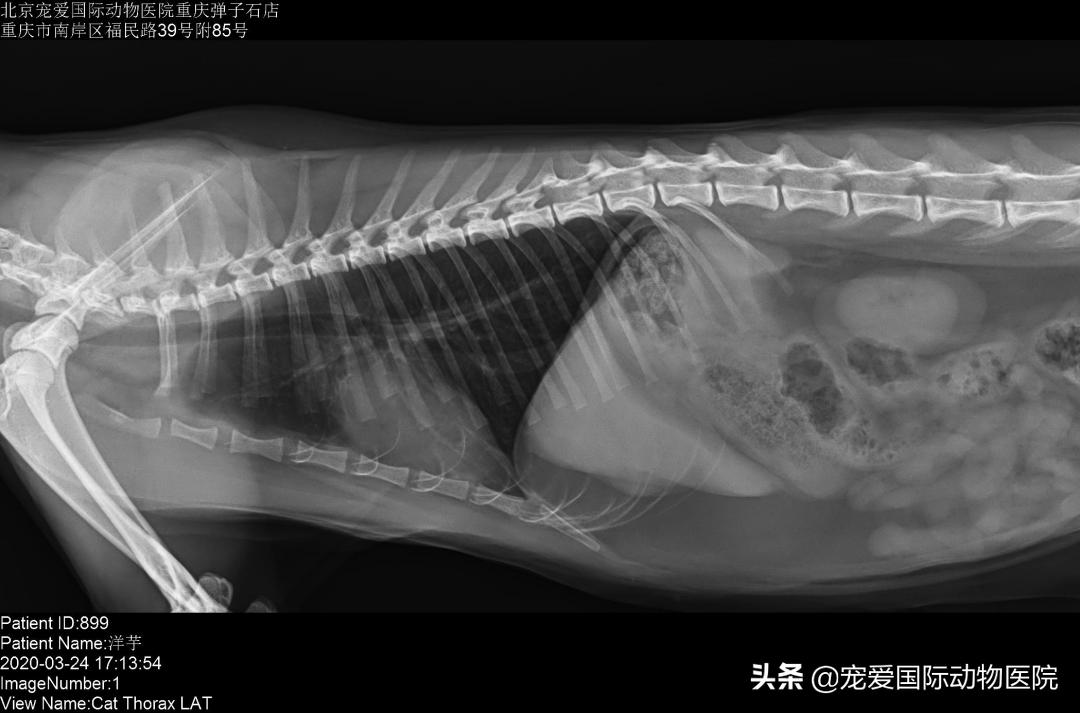

经过一周治疗,洋芋呼吸情况明显好转,食欲恢复正常,精神良好,排便情况正常,复查x光胸水逐步在减少,肺叶逐渐恢复正常。继续用药到3周复查,胸水消失,各项指标恢复正常。整体治疗效果良好,遂出院。

治疗第三周肺叶逐步恢复正常,胸水消失。